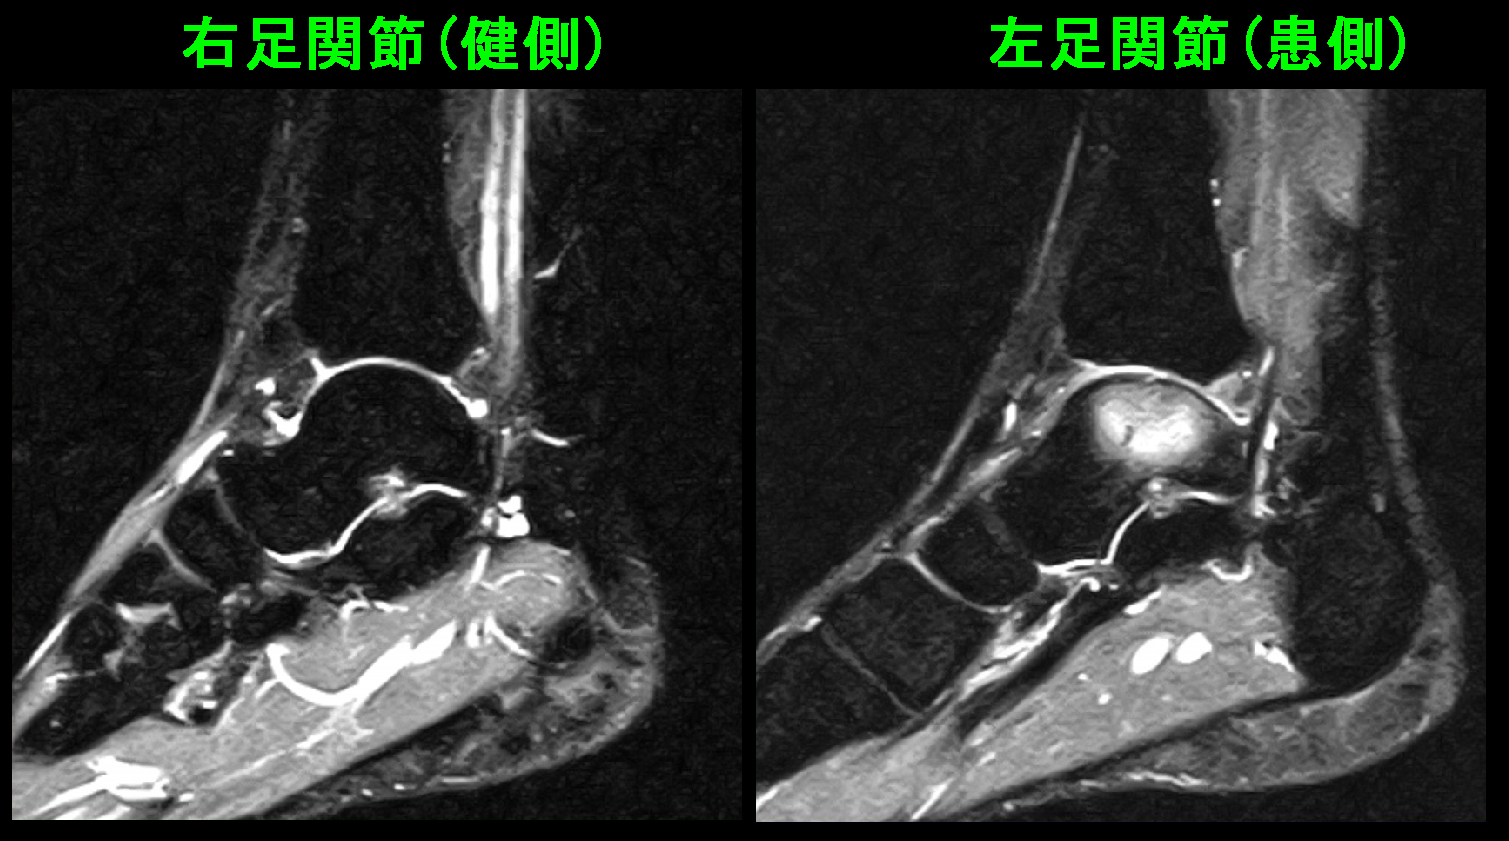

患者さんの訴える経過の長さと発症する症状の強さから、MRI検査を行えば必ず異常所見を確認できるはずと推察し、MRI検査を勧めました。

上図のSTIR条件のMRI画像では患側の左足関節の距骨という骨が白くなっています。これは骨内の出血と同様の所見で疲労骨折と評価して良い所見です。

また距骨の足関節面はきれいな円形でなくなっています。これは疲労骨折により劣化した距骨に体重負荷がかかり続けて円形の関節面が変形したものと理解されます。

T1という条件のMRI画像では距骨は黒くなって損傷所見を意味し、脛骨(下腿側の骨)の関節面の軟骨が健側に比して黒っぽくなっており、これは関節軟骨の変性を意味し、この状態が進行すると将来にわたり日常生活での左足関節痛が続くようになるリスクを示す所見です。距骨の骨の形態が多少変形したように、このままスポーツを続けていれば、左足関節は変形性関節症に進行していく過程にあると理解されます。

患者さんは近々予定されている大事な野球の試合に痛みがでないような治療を期待していたようですが、私は一応薬を処方し、2か月スポーツを休止しなければ距骨の骨損傷はずっとそのまま改善しないままとなり、将来日常生活でのもずっと左足関節痛と付き合わなければならないようになる可能性を説明しました。

10か月後に患者さんは腰痛で再診されましたが、6週間スポーツを休止して、症状は治癒したと報告してくれました。